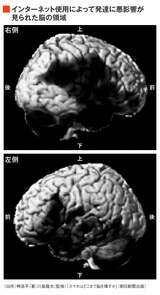

スマホが学力を「破壊」する、成績不振は勉強不足や寝不足ではなかった新事実 中高生4人に1人が「ネット依存」の恐ろしさ